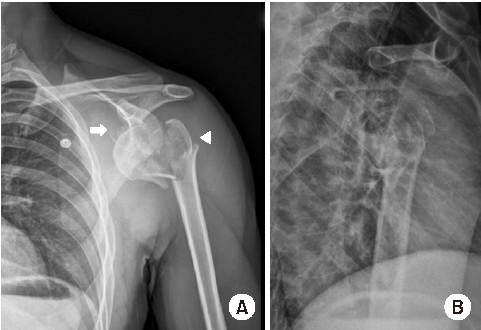

Shoulder joint dislocation has the most common incidence rate compare compared to other joints. It is reported that shoulder Shoulder dislocation couldmay be associated with glenoid rim, greater tuberosity of humerus and coracoid process fracture. There were have only been 2 cases of anterior shoulder dislocation simultaneously combined with simultaneous glenoid rim, coracoid process, and humerus greater tuberosity fracture worldwide and no report reports in Korea. We present a case of quadruple fracture (glenoid rim, coracoid process, greater tuberosity, surgical neck of humerus) associated with anterior shoulder dislocation and treated successfully by open reduction. In addition, with we provide the injury mechanism, diagnosis, treatment procedure and discussion.